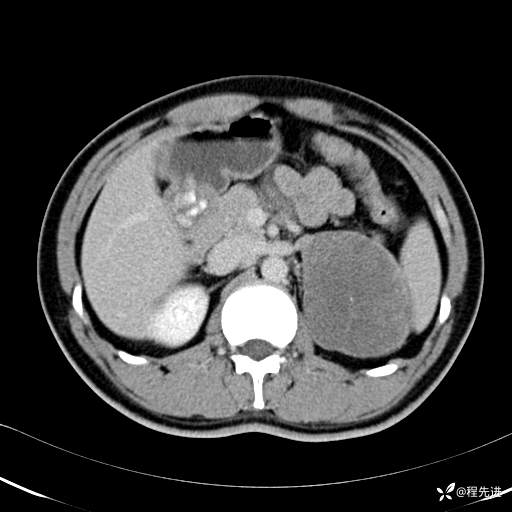

【腹盆】特别精彩病例|体检发现的左侧腹膜后占位期待您的精彩解读

患者年龄:25岁

简要病史:体检发现

CT平扫:(CT值:平扫,27HU,动脉期,27HU,门静脉期,31HU,平衡期,32HU)

冠状位重建:

矢状位重建: